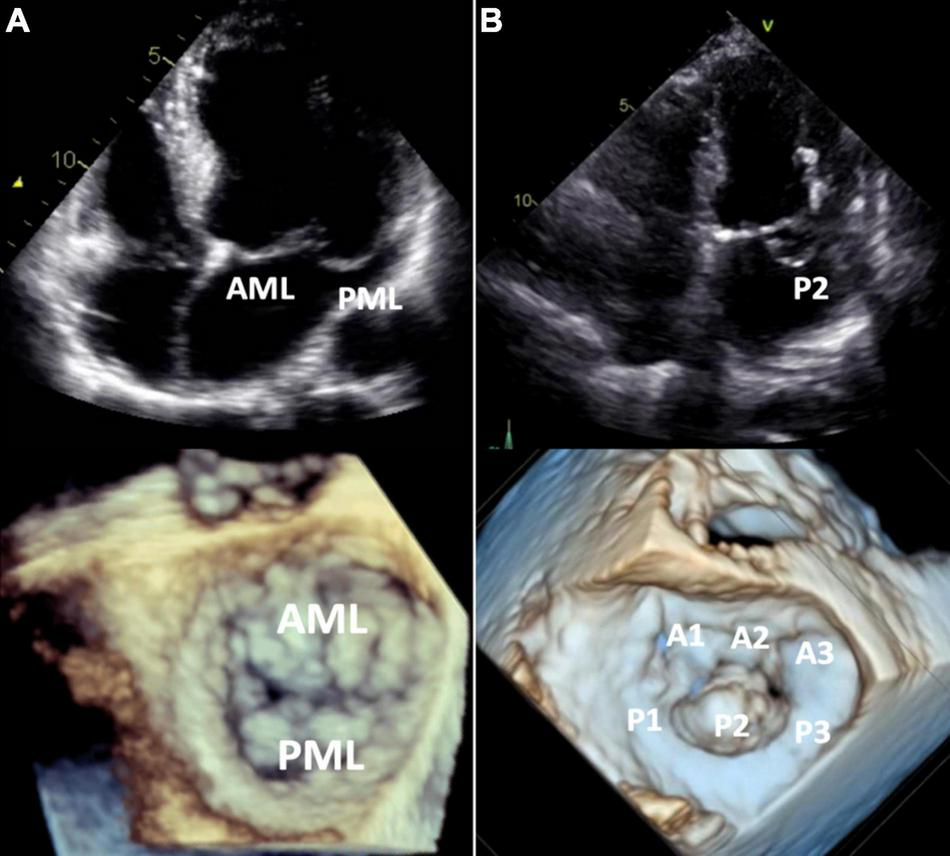

Following diagnosis of prolapse, MVP subtypes (BD vs. FED) can be differentiated by comprehensive echocardiographic assessment (Figure 4).

FIGURE 4

Barlow’s disease vs. fibroelastic deficiency. 2D transthoracic four-chamber view (upper panels) and 3D transesophageal focused view of the mitral valve (lower panels). (A) Barlow’s disease with annular dilatation, thickened leaflets and bileaflet prolapse (anterior + posterior mitral leaflet). (B) Fibro-elastic deficiency with prolapse (flail) of the P2 segment of the posterior mitral leaflet due to chordal rupture. Mitral annulus diameter is normal in this case, but mild annular dilatation can be present. AML, anterior mitral leaflet; PML, posterior mitral leaflet.